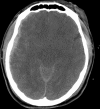

Traumatic intracranial pseudoaneurysms are a rare but severe complication following arterial injury. Pseudoaneurysm formation can occur secondary to blunt or penetrating trauma or iatrogenic injury. We report a case of traumatic pseudoaneurysm secondary to placement of an intracranial pressure (ICP) monitor. A 27-year-old man was involved in a motorcycle accident resulting in multiple intracranial hemorrhages. The patient underwent craniectomy and placement of an ICP monitor. 17 days later he developed dilation of his left pupil, with imaging demonstrating a new hemorrhage in the vicinity of the previous ICP monitor. A cerebral angiogram confirmed a left-sided distal M4 pseudoaneurysm which was treated by n-butyl cyanoacrylate embolization. Intracranial pseudoaneurysm formation following neurosurgical procedures is uncommon. Delayed intracranial hemorrhage in a region of prior intracranial manipulation, even following a procedure as 'routine' as placement of an ICP monitor, should raise the suspicion for this rare but potentially lethal complication.